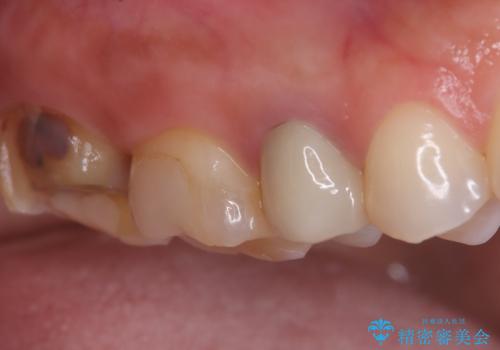

虫歯 〈セラミックインレー〉

- 初診時にお口の中をチェックしたところ虫歯があり、大きさから部分的な詰め物のお話をしました。材料の特性を説明し、再び虫歯になりにくいセラミックインレーを選択されました。

セラミックインレー接着時にはラバーダム防湿を行いました。